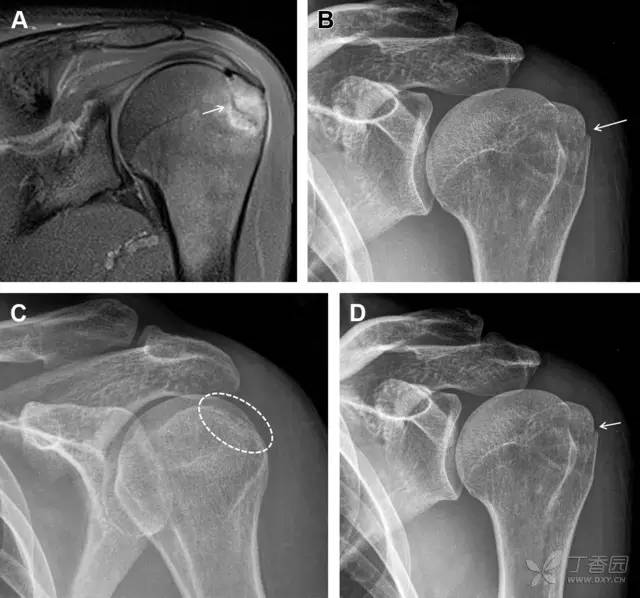

在常规前后位片上,大结节与肱骨头重叠,骨折不易发现,外旋位前后位片有助于诊断。

图 1 大结节骨折。(A)脂肪抑制序列斜冠状位 MRI,显示肱骨大结节线性骨折无移位(箭头)与周围骨水肿;(B)外旋位前后位(AP)片,证实大结节骨折(箭头),典型的骨折愈合过程中的骨吸收表现;(C、D)初诊时内旋位、外旋位前后位片,初诊时漏诊,仔细回顾影像,内旋伞下可见双密度影(椭圆),骨皮质中断(箭头)